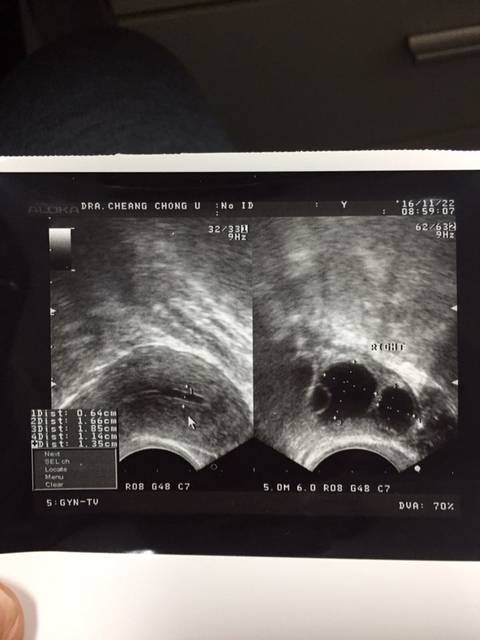

B超显示宫腔分离严重吗?

640x854 - 56KB - JPEG

帮忙看看_宫腔分离严重吗怀孕一个月

480x640 - 23KB - JPEG